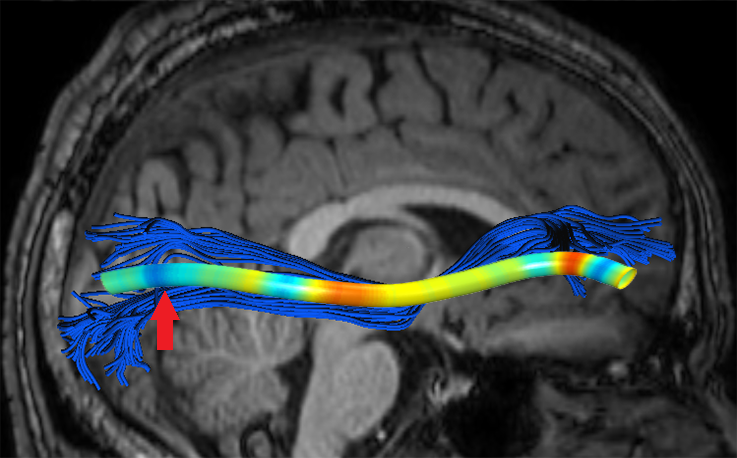

We performed pairwise comparison between two scans of a 32-year-old basketball player, diagnosed with mild occipital traumatic brain injury and frontal hemorrhage due to contrecoup impact, acquired one week and 6 months post-injury. The hemorrhagic lesion at the frontal right hemisphere of the player is no longer visible in the FLAIR image acquired 6 months after injury (Fig. 2a). Local differences between corresponding, longitudinal FA- and MD-FFDD profiles of the FMT (chosen due to its proximity to the lesion area) are shown in Fig. 2d. Figs. 2b-c present color-coded FMT to visually demonstrate these differences. Results show significant longitudinal variability at the right hemisphere part of the tract, corresponding to the lesion area, and relatively minor differences along the rest of the tract. These results should be considered as a proof of concept, validating the FFDD analysis results for the detection and localization of mTBI-related variabilities between fiber bundles.

| ONE WEEK | ![]() |

![]() |

FA-FFDD |

| 6 MONTHS | ![]() |

MD-FFDD |

| (a) FLAIR | (b) FA-FFDD | (c) MD-FFDD | (d) Local Differences |